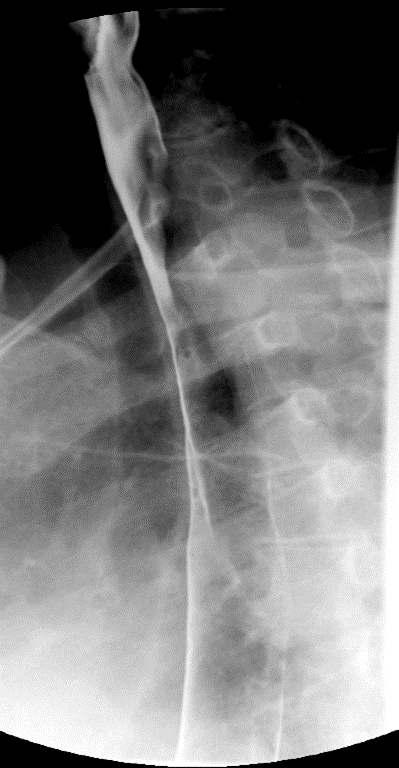

- Method—Cervical:

- Start with the patient in the upright lateral position.

- Ensure the fluoro machine is set to 4 images per second (rapid sequence).

- Explain to the patient that you are going to have them take a "comfortable mouthful" of barium and that they will need to hold it in their mouths until you count to 3.

- Make sure they understand that they are not to swallow until the count of 3.

- Once the patient has taken the "comfortable mouthful" of barium, center the fluoroscope on the cervical esophagus.

- Once the fluoroscope is properly positioned, begin counting. On the count of 2, begin taking rapid sequence images of the contrast material bolus as it moves through the cervical esophagus

(key image 1)

- Take the fluoroscope off rapid sequence.

- With the patient in the lateral position, obtain a spot film of the pharynx and cervical esophagus while they phonate the letter "e"

(key image 2).

- Repeat steps 4-7 with the patient in the AP position

(key image 3)

(key image 4).

- Cervical images are obtained in the lateral and AP projections as the patient swallows thick barium.

- Cervical image are obtained using rapid sequence fluoroscopic spot films at a rate of 4 frames per second.

- To time this appropriately, you will count to 3. You will begin to take images on 2, the patient will swallow on 3.